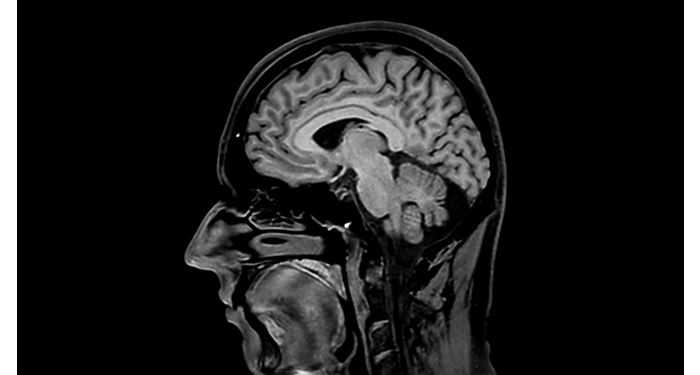

70% of radiologists consider neuro indications to be challenging, mostly due to a lack of appropriate imaging and visualization techniques¹. Philips aims to provide the best possible diagnostic clarity and treatment guidance for all patients with neurological disorders. By leveraging our dStream digital platform, this year, we are introducing, a set of novel imaging and visualization strategies. These may empower you to resolve complex neuro questions with more certainty, as well as unlock new neuro territories in advanced Neurofunctional applications. This is a key step towards elevating neuro diagnostics and ultimately touching more lives with MR imaging. ¹ TMTG Market Survey 2016

New neuro applications

MR Body Map

Clinical cases from nearly every anatomy Explore 100+ clinical cases from your peers around the globe, that showcase how Philips MR digital technology strengthens your imaging needs.